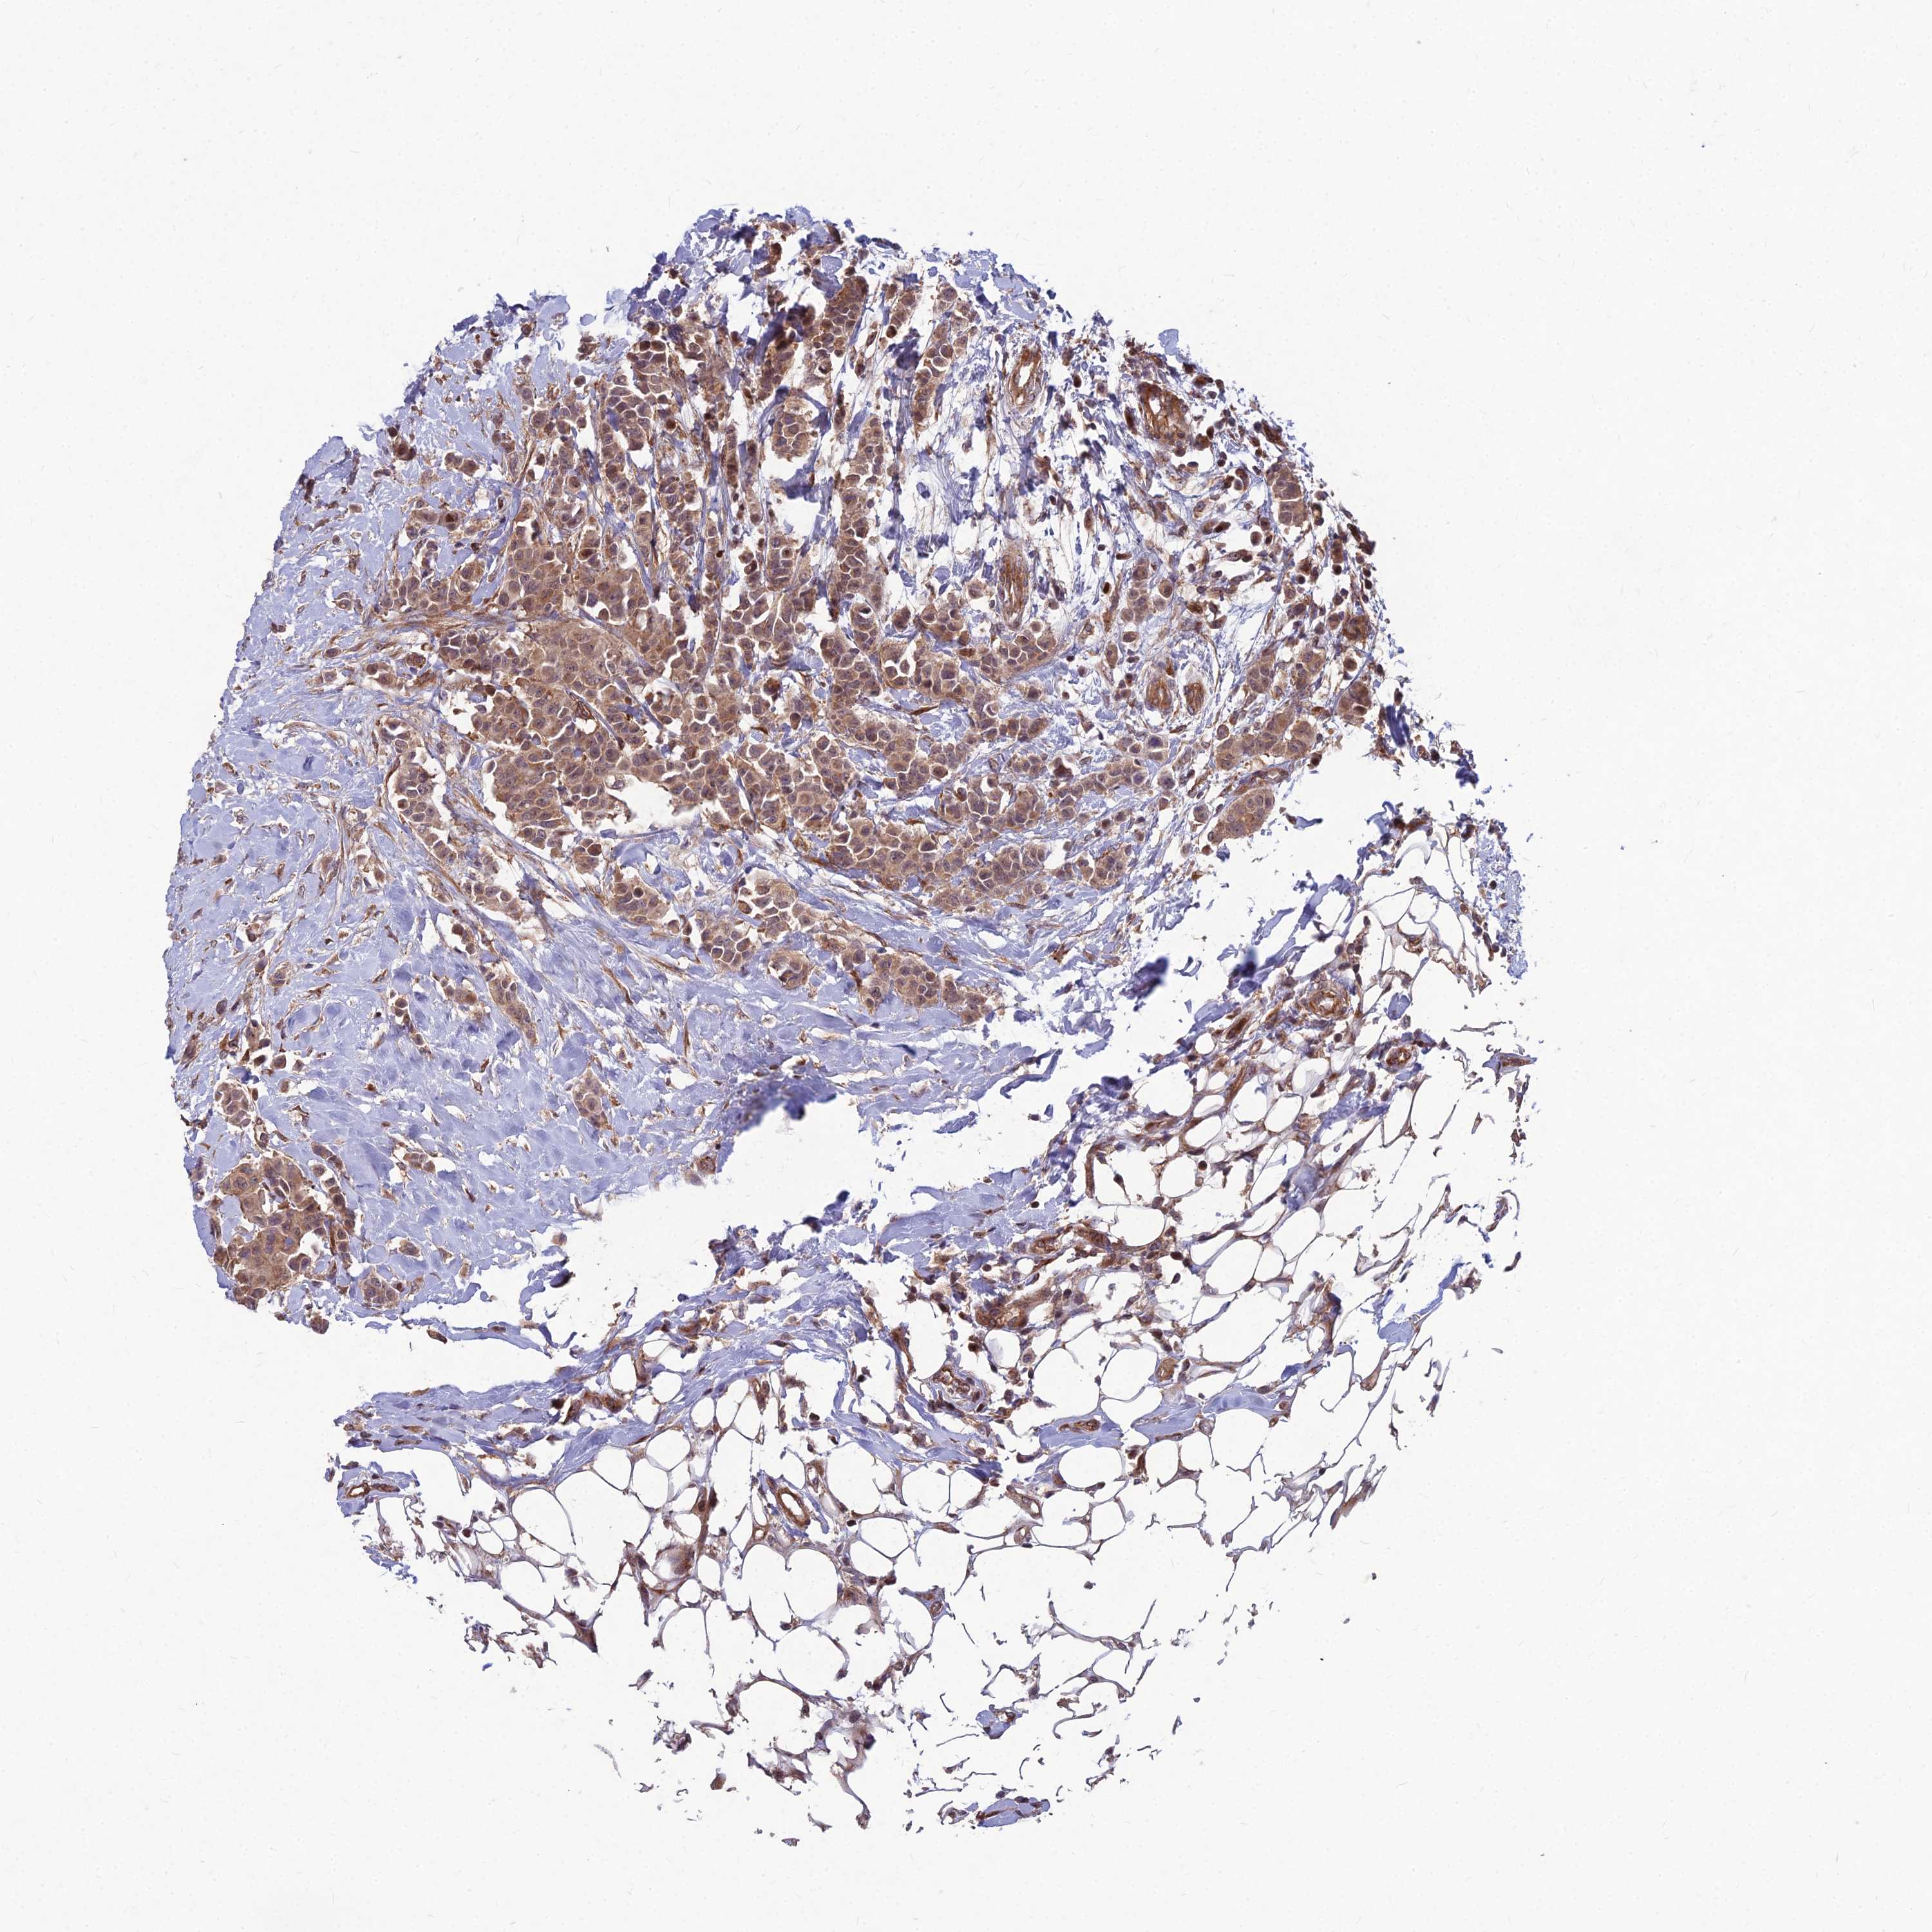

CANCER BREAST CANCER Show tissue menu

BRCA TCGA BRCA VALIDATION PROTEIN EXPRESSION